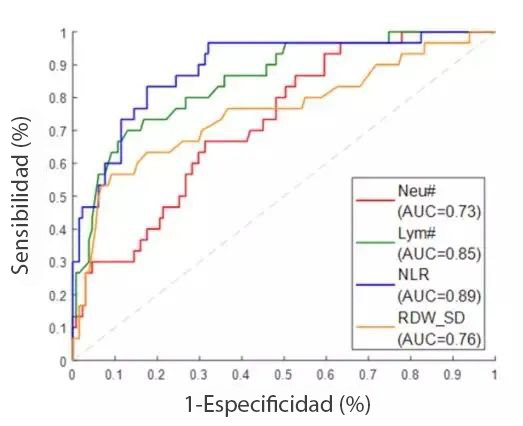

El primer diagrama que aparece a continuaciÃġn muestra la curva caracterÃstica operativa del receptor (ROC, por sus siglas en inglés) de casos graves de COVID-19 distinguidos de los moderados mediante parÃḂmetros hematolÃġgicos. Las muestras positivas que se muestran aquà son resultados de hemogramas de casos graves, y las muestras negativas corresponden a los casos moderados. Los resultados muestran que el NLR es el mejor parÃḂmetro Ãẃnico para distinguir los casos graves de los moderados,?con un ÃḂrea bajo la curva (AUC, por sus siglas en inglés) de 0,89.

Una curva ROC es una forma de comparar pruebas de diagnÃġstico. Es un grÃḂfico de la tasa de verdaderos positivos frente a la tasa de falsos positivos. Un grÃḂfico de curvas ROC muestra la relaciÃġn entre la sensibilidad y la especificidad. Por ejemplo, una disminuciÃġn de la sensibilidad supone un aumento de la especificidad.